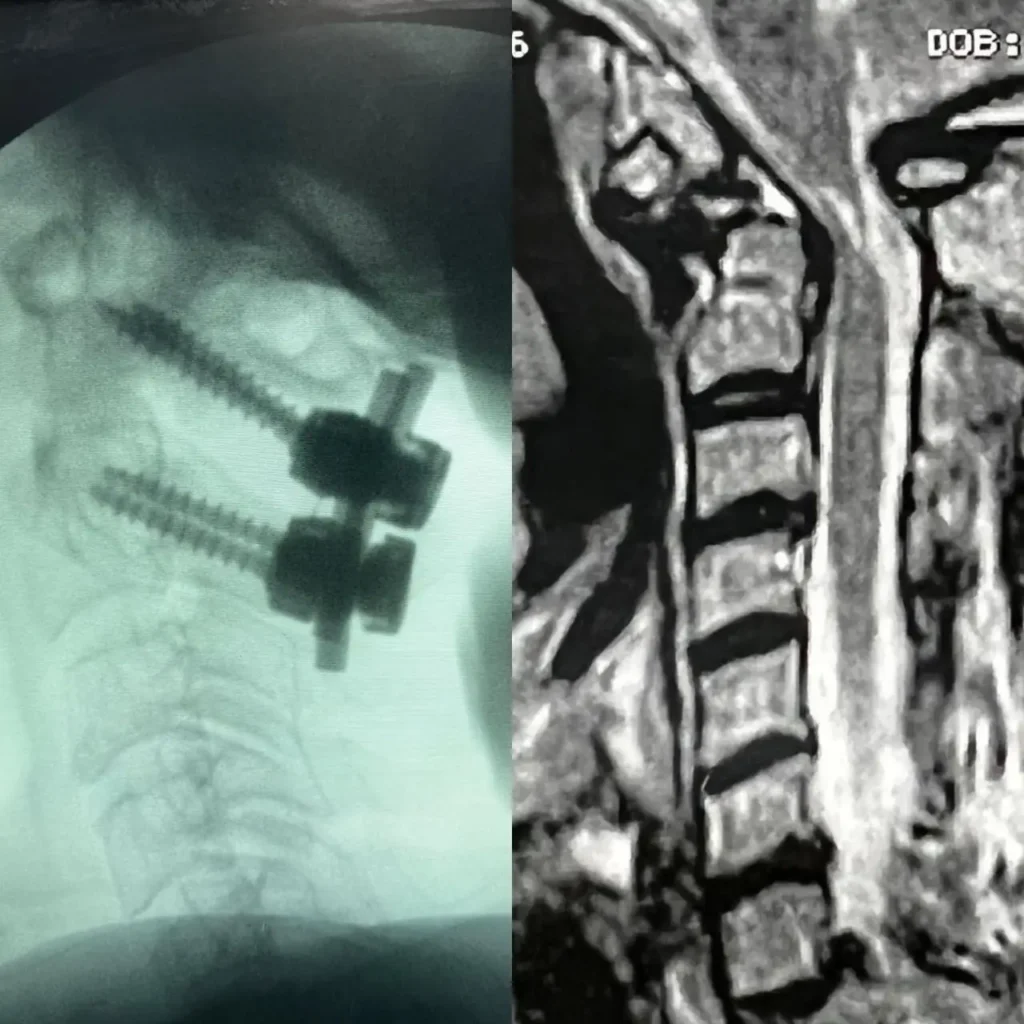

Artrodese Cervical Via Posterior

Cirurgia que estabiliza a região cervical pela parte posterior da coluna, indicada para instabilidades, desgastes avançados e compressões nervosas, oferecendo maior segurança e alívio da dor.

Artrodese da Coluna Minimamente Invasiva

Procedimento que estabiliza a coluna através de pequenas incisões, reduzindo dor, sangramento e tempo de recuperação em comparação à técnica tradicional.